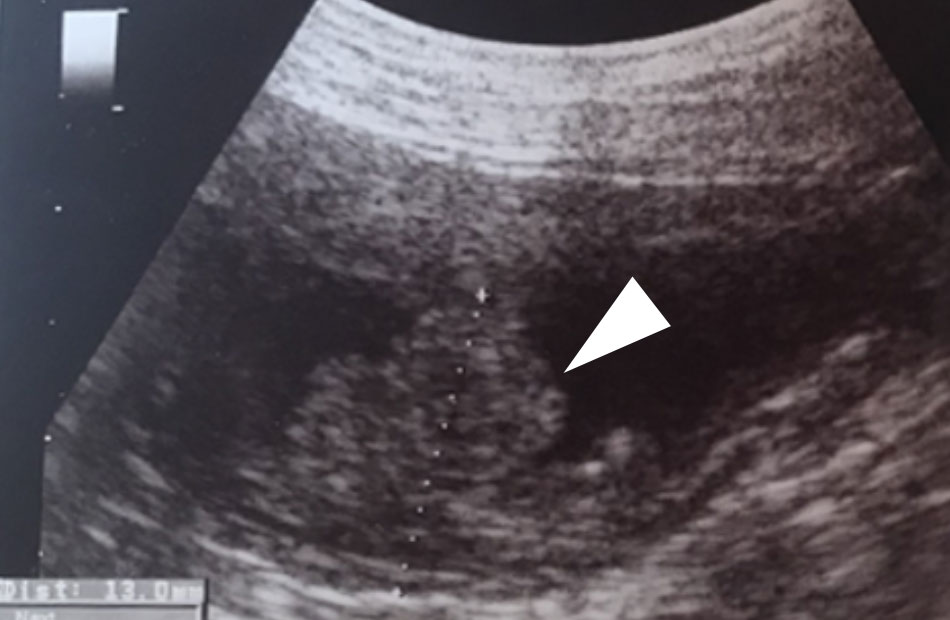

腹部超音波検査/CT検査

膀胱の一部(尖部)に約1.3cmの腫瘤を認めました(図の白矢印)。